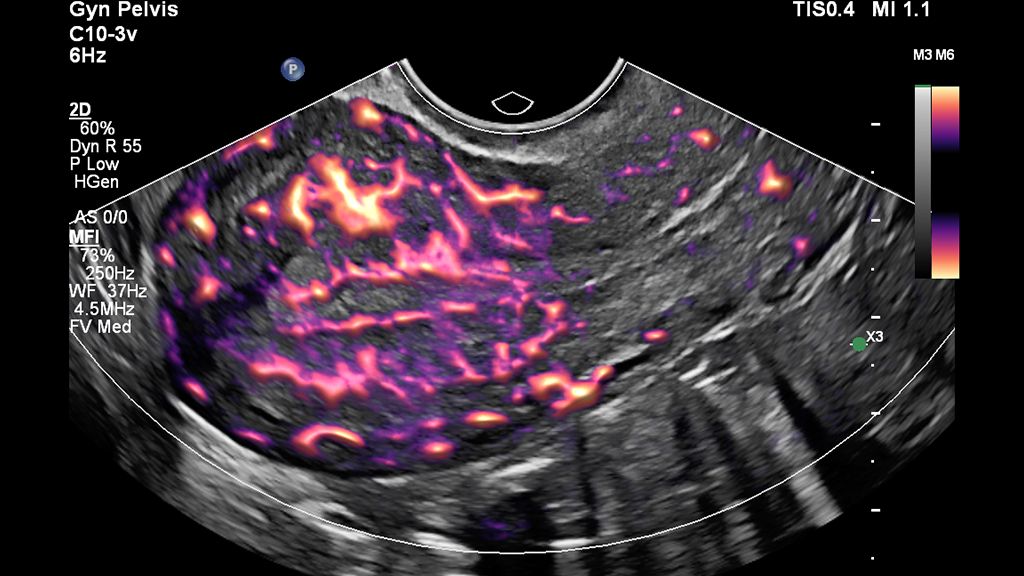

• MicroFlow HD detects low-volume, low-velocity blood flow in uterine and ovarian vasculature with high resolution, minimal artifacts and a high frame rate.

• Clinical image of uterus obtained with MicroFlow imaging (MFI) and Flow Viewer

MFI with Flow Viewer image of the uterus

• MicroFlow Imaging

MicroFlow (MFI) and MicroFlow-HD (MFI-HD) imaging mode

Available on Philips ultrasound transducers, MicroFlow Imaging (MFI) and MicroFlow HD (MFI-HD) detect slow and weak blood flow anatomy in tissue.

• Flow Viewer advanced visualization

Flow Viewer 3D advanced visualization

Available on Philips ultrasound machines, Flow Viewer defines vasculature with a 3D-like appearance and reduced flash artifact.